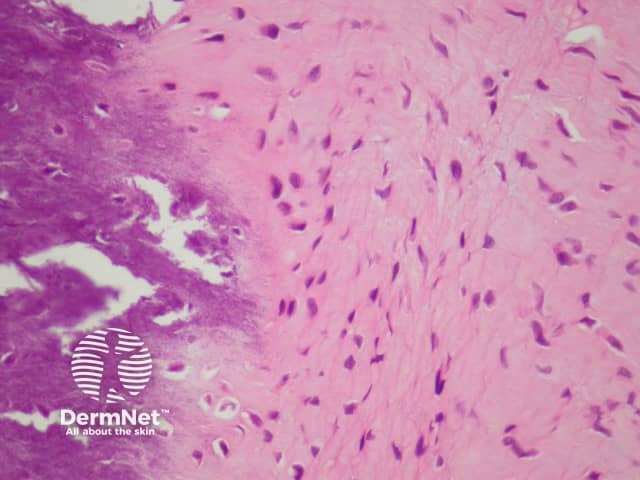

In calcifying aponeurotic fibroma, sections show an irregularly shaped dense mass of fibrous tissue with foci of calcification (figures 1, 2). The fibrous tissue is quite cellular and appears to infiltrate the surrounding adipose tissue (figure 1).

Figure 1

Figure 2